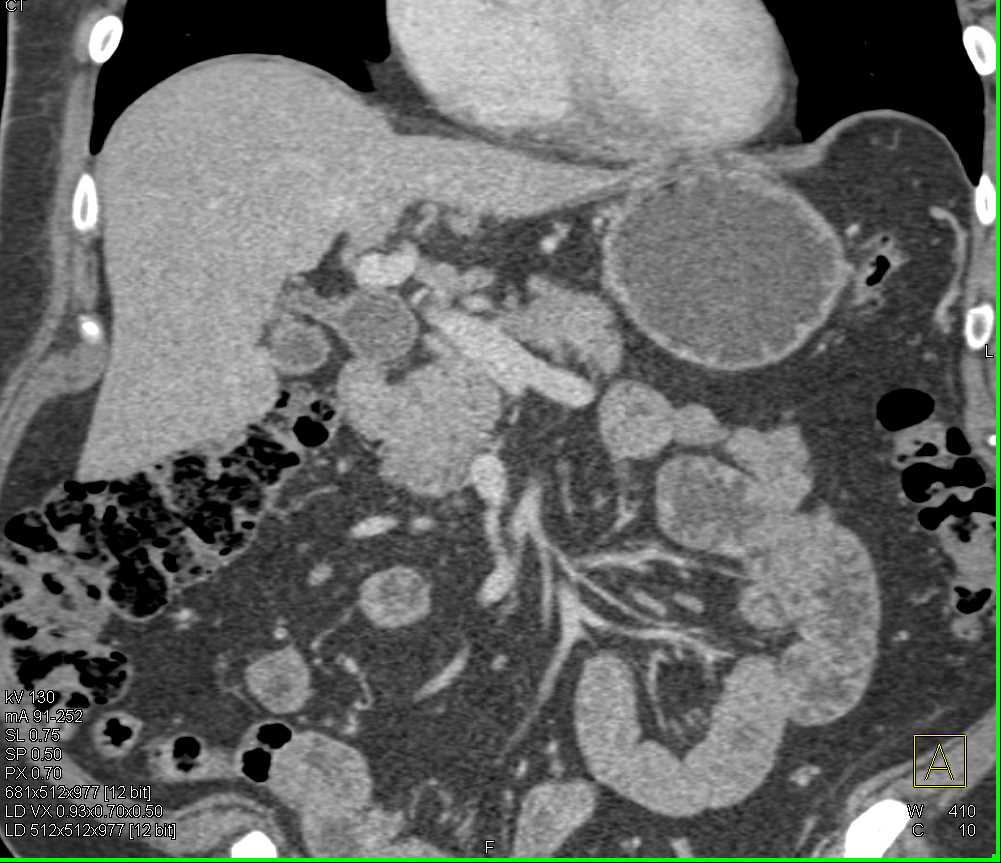

Professors Satomi Kawamoto and Professor Elliot K. Fishman (@ctisus), Associate Professor @LindaChuMD (@LindaChuMD), and Research Fellows Mohammad Yasrab and Juan Felipe Lopez-Ramirez (@FelipeLopezMD), presented an educational exhibit on βThe Challenges in the Detection and